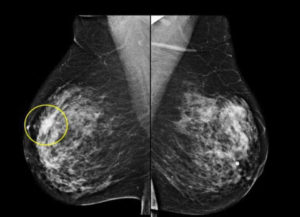

После первичного обследования по показаниям или с профилактической целью врач-маммолог назначит следующие исследования:

- маммография (после 35 лет при подозрении на фиброзную патологию проводить ультразвуковое исследование не информативно);

При обнаружении узловой или кистозной формы ФКМ обязательным этапом обследования является проведение пункционной биопсии под контролем УЗИ, которое поможет исключить пролиферативные и предраковые процессы в груди.

УЗИ молочных желез можно проводить женщинам до 35 лет. При исследовании врач увидит следующие эхопризнаки фиброзных изменений:

- очаги уплотнения разного размера и без четких контуров;

- возможно наличие мелких кист.

Как показывают отзывы врачей, с помощью УЗИ можно диагностировать узловые и кистозные формы заболевания. Для выявления фиброза лучше использовать маммографию.